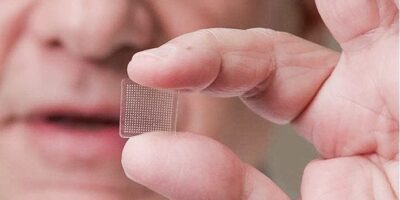

Pain management during dental procedures is a cornerstone for successful daily practice. In current practice, the traditional ...